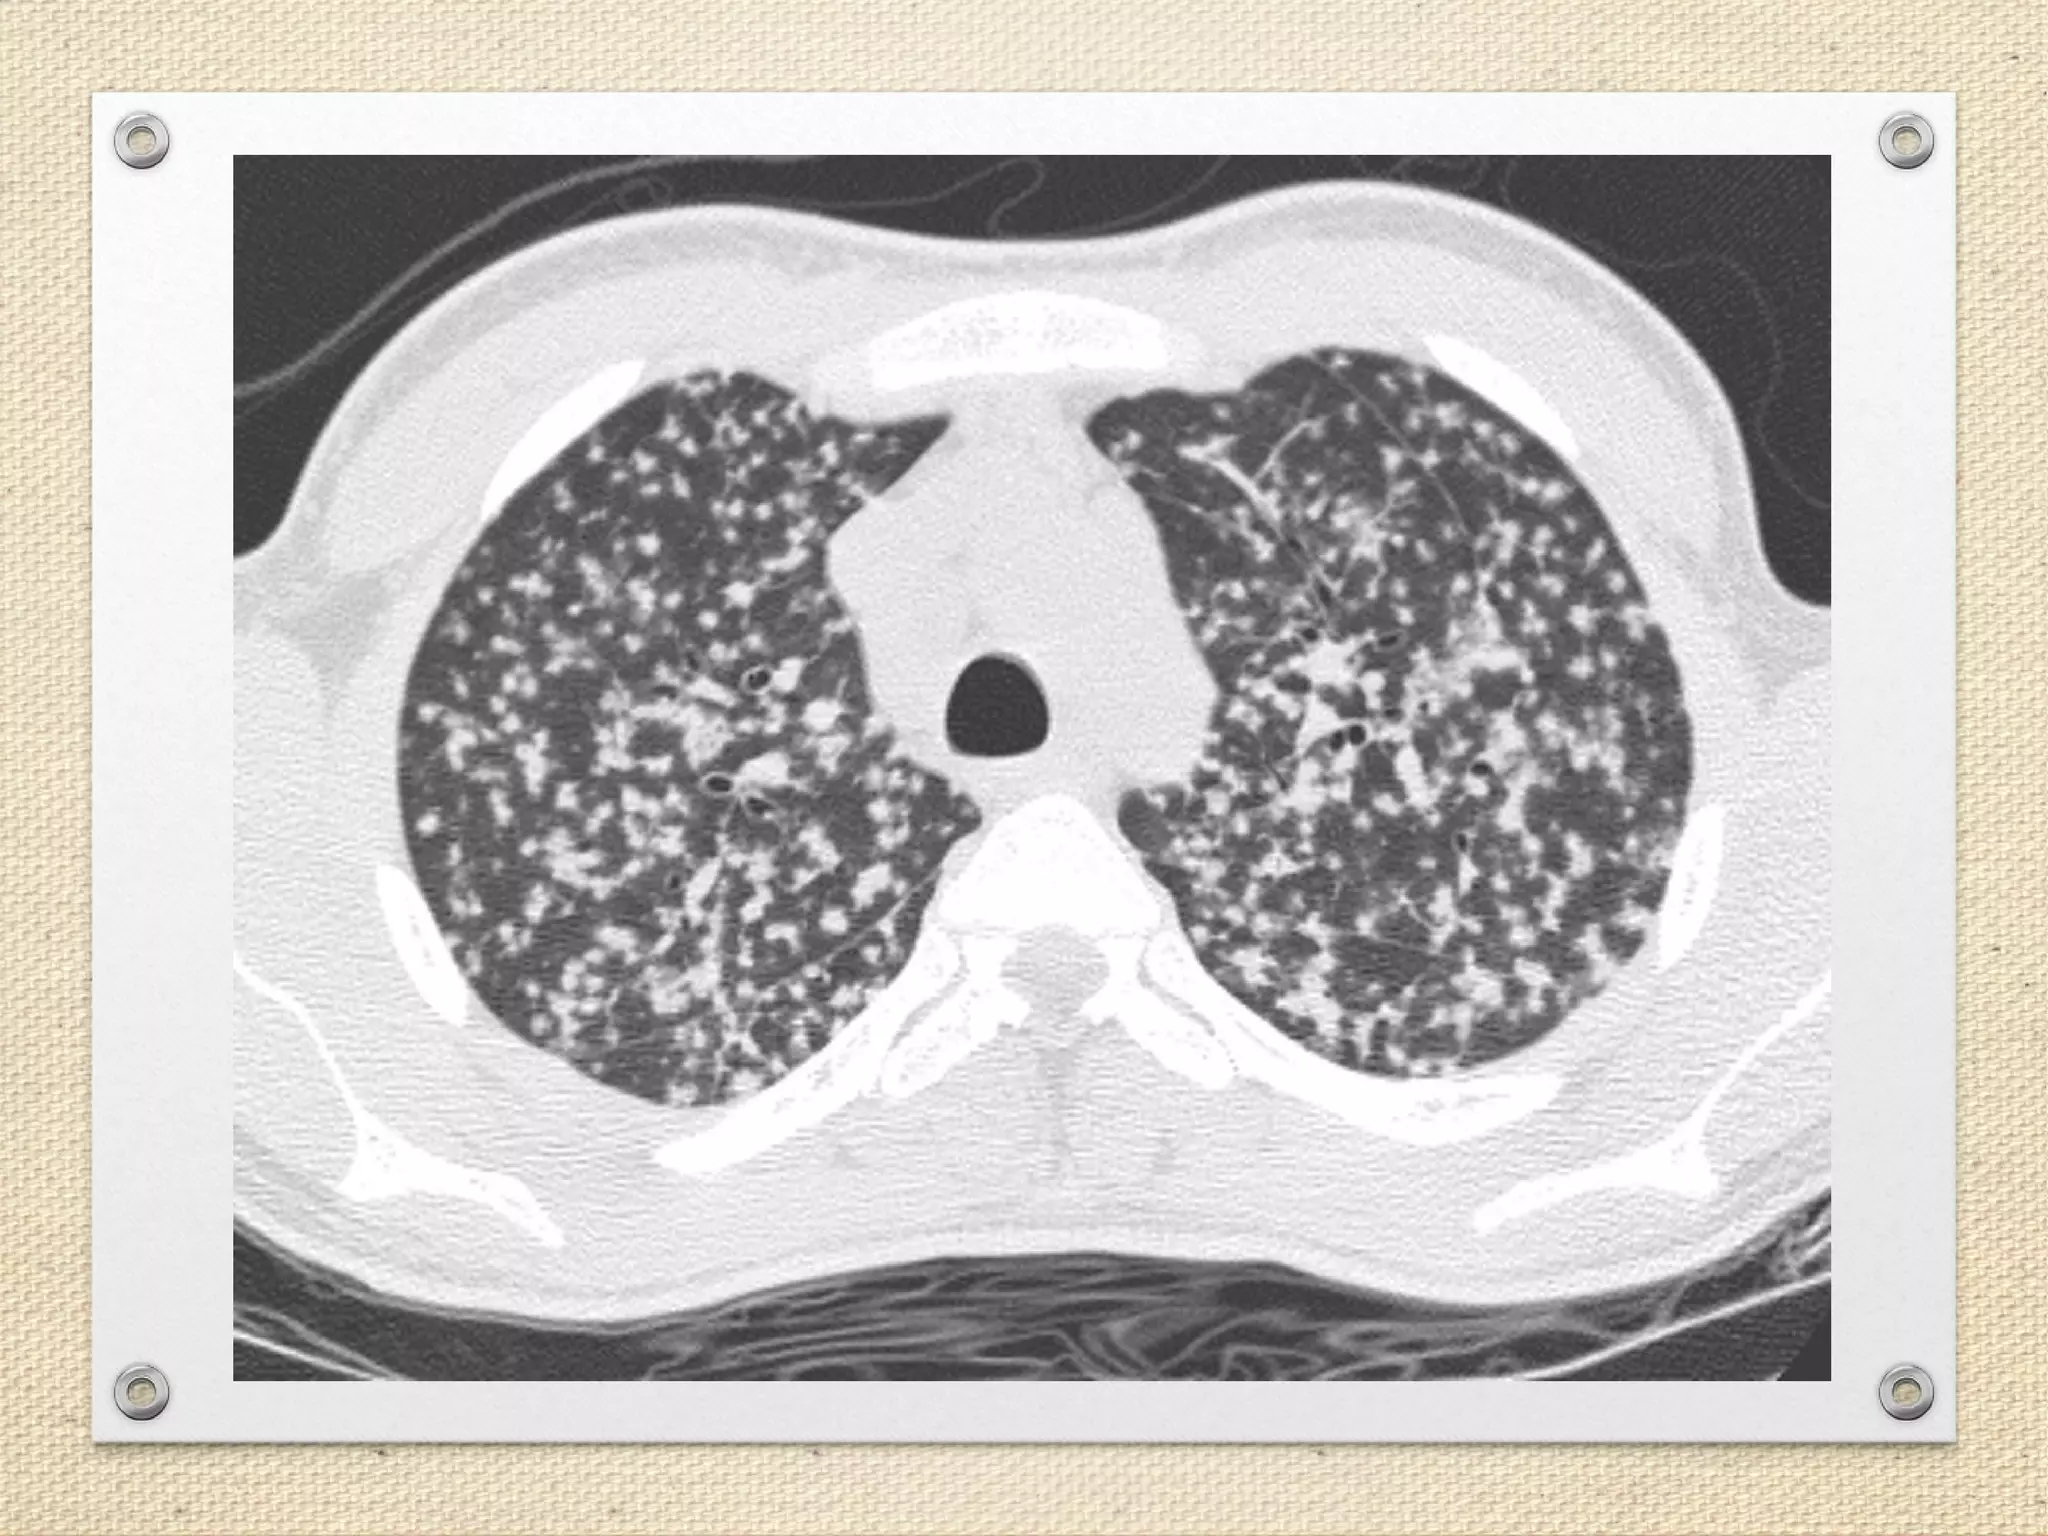

Miliary Tuberculosis with Acute Respiratory Distress Syndrome: A Deadly Combination | Cureus

Imaging of Pulmonary Miliary Tuberculosis With Multiple Intracranial Tuberculomas | Cureus

Miliary Lung Lesions Mimicking Tuberculosis: A Case of Metastatic Lung Adenocarcinoma | Cureus

image size: 986x897